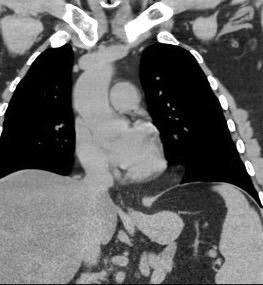

Tromboembolismo pulmonar Diafragma elevado 20%

Consolidación por Infarto pulmonar. (TEP)

Borramiento del hemidiafragma derecho

“Visible en toda su longitud en lateral”.